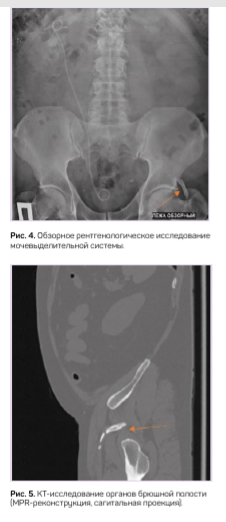

На обзорной урограмме с захватом лонного сочленения у пациента М. была обнаружена костная структура с фалангообразной перемычкой в области левого тазобедренного сустава, связанная с телом подвздошной кости (рис. 4). Эта «находка» соответствовала ранее найденному «тазовому пальцу» у пациента С. Компьютерно-томографическое исследование показало костную структуру с четким кортикальным слоем (рис. 5).